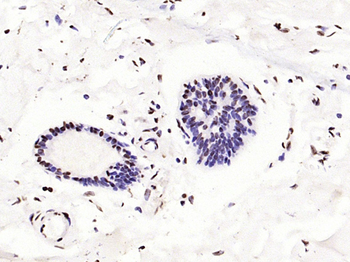

100 μl, 50 μl, 25 μl - Rad51 Recombinant Rabbit Monoclonal Antibody [orb608069]Featured

IF, IHC-Fr, IHC-P, WB

Human, Mouse, Rat

Mouse, Rat

Rabbit

Recombinant

Unconjugated

50 μl, 100 μl - KLF4 Recombinant Rabbit Monoclonal Antibody [orb608075]Featured